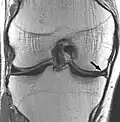

| Proton density weighted | PD | Long TR (to reduce T1) and short TE (to minimize T2).[56] | Joint disease and injury.[57]

|